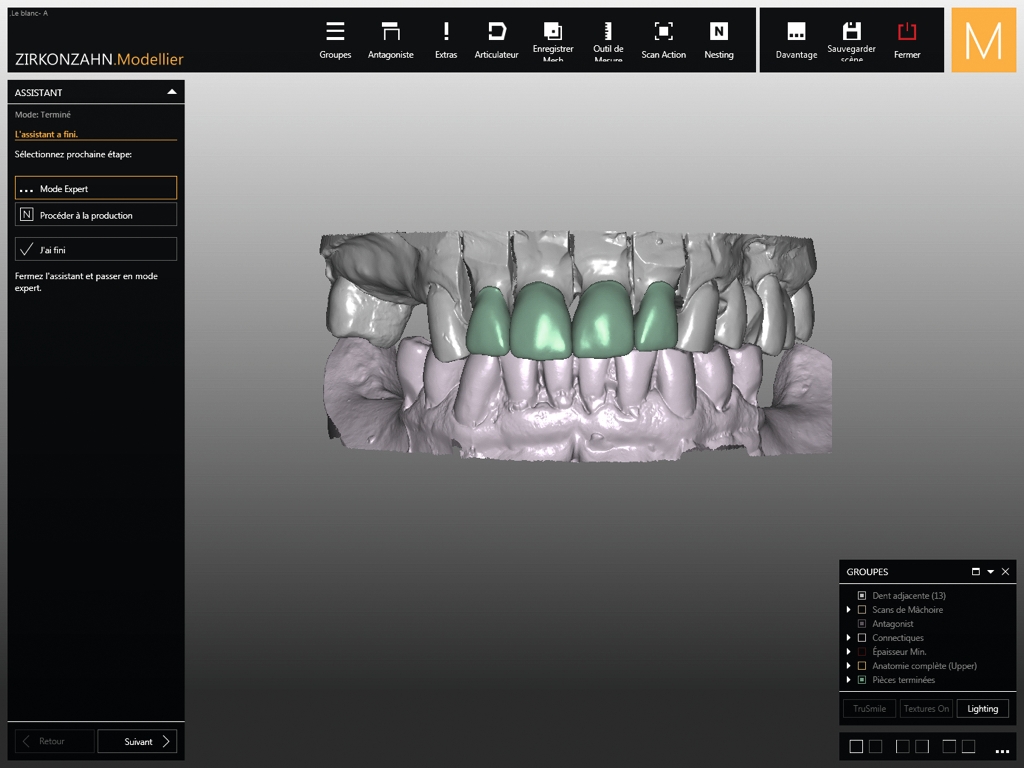

Fig. 6 : Wax-up numérique des couronnes.

Quatre jours plus tôt, la figure 6 montre le wax-up numérique (logiciel Zirkonzahn.Modellier, Zirkonzahn). Pour le prothésiste dentaire, la difficulté principale a été de repenser l’anatomie des incisives maxillaires, tout en réhabilitant la forme initiale des dents. La forme globale des autres dents donne un aperçu de la typologie géométrique des dents : rondes, carrées, triangulaires. Toutes les formes sont possibles mais une seule forme est adaptée à ce cas clinique. Le logiciel de CAD/CAM permet un guidage automatique, pour obtenir uniforme harmonieuse. Puis le technicien de laboratoire va reprendre la main et procéder individuellement, afin d’apporter des touches humaines à un système informatique.